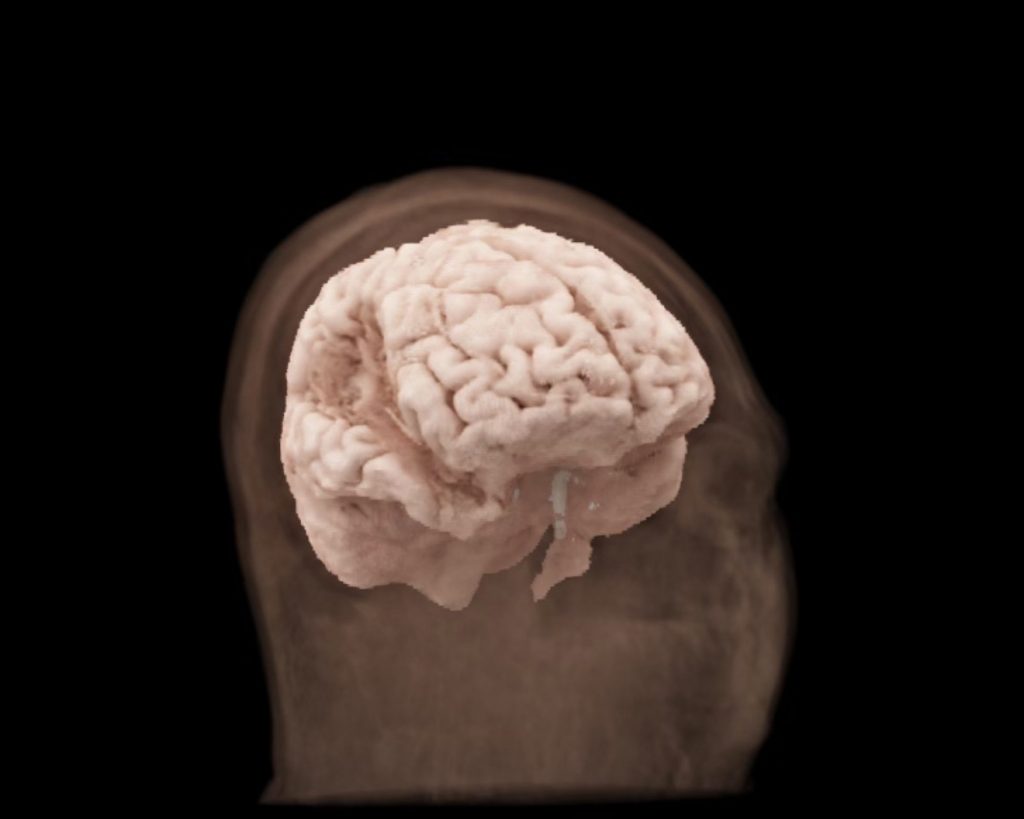

Common Neurological Conditions Impacted by Disparities

While all brain conditions are challenging, disparities can make them even harder to manage. Lack of access to proper nutrition, specialized care, and resources can worsen symptoms and slow recovery for many common neurological issues.